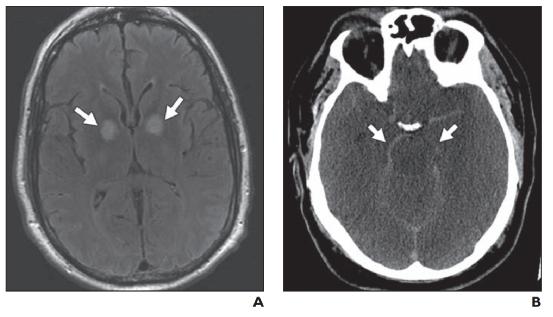

3.间质性水肿

间质性(脑积水)水肿发生在脑室内压升高的情况下,这会导致脑室室管膜内层破裂。这允许脑脊液经室管膜迁移到细胞外空间,最常见的是脑室周围白质。液体成分与 CSF 相同,具有相似的离子浓度和可忽略不计的蛋白质(与血管源性水肿相反)。间质性水肿的各种原因包括阻塞性肿块、脑膜炎、蛛网膜下腔出血和正常压力脑积水。相比之下,颗粒性室管膜炎是指前外侧额角周围的小三角形异常信号区域(图 11 )). 这种正常的解剖变异是由于局部髓鞘减少、细胞外液增加或室管膜内层局部破裂伴神经胶质增生所致。在 CT 上,脑室扩大和脑室周围低密度增加的组合提示间质性水肿的诊断(图 12A )). MRI 是一种更敏感的成像方式,在 T1 加权成像上显示低信号,在 T2 加权成像/FLAIR 上显示脑室周围高信号(图 12B )). 脑室周围高信号可根据其严重程度分级。1 级(不连续)表现为靠近额角和枕角以及侧脑室的局灶性信号异常。2 级和 3 级(连续和脑室周围晕)完全围绕脑室并且厚度不同。4 级(弥漫性白质异常)延伸至灰白质交界处。由于水肿位于细胞外,DTI 图可能显示局部各向异性分数降低。然而,平均总体扩散率在 DWI 和 ADC 图上是正常的。

对于有症状的患者,通过切除阻塞性病变(非交通性脑积水)或放置脑室造瘘管(交通性脑积水)进行减压可使脑室压力恢复正常。反过来,这使得间质液能够正常顺行吸收穿过室管膜内层并回到脑室系统。如果不进行干预,这些发现最终会发展为脑萎缩和神经胶质增生。